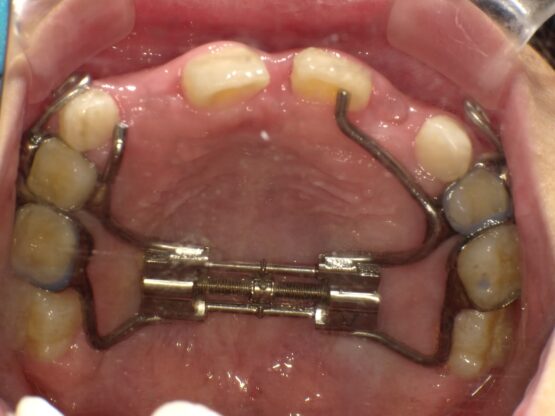

上顎の骨には繋ぎ目が存在しており、そこで左右二つの骨に分かれています。急速拡大装置を上顎に固定して装置の中央にあるネジを回すことで繋ぎ目を広げ、徐々に上顎の骨の変えていきます。そうすることで、顎の骨が正しい形に成長していくよう促され、永久歯を正しい位置で生えるように誘導できます。

急速拡大装置で上顎の拡大が進むと、下顎の骨も調整する必要が出てきます。その際に使う装置がリンガルアーチです。下顎の骨は上顎の骨と作りが違います。下顎はひとつの骨で構成されているので、上顎と同じように拡大させることができません。内側に傾いている歯を起こすようにして歯列部分だけを拡げていきます。この装置も固定式の装置となっており、歯の裏側に装着しますので目立たない見た目となっています。